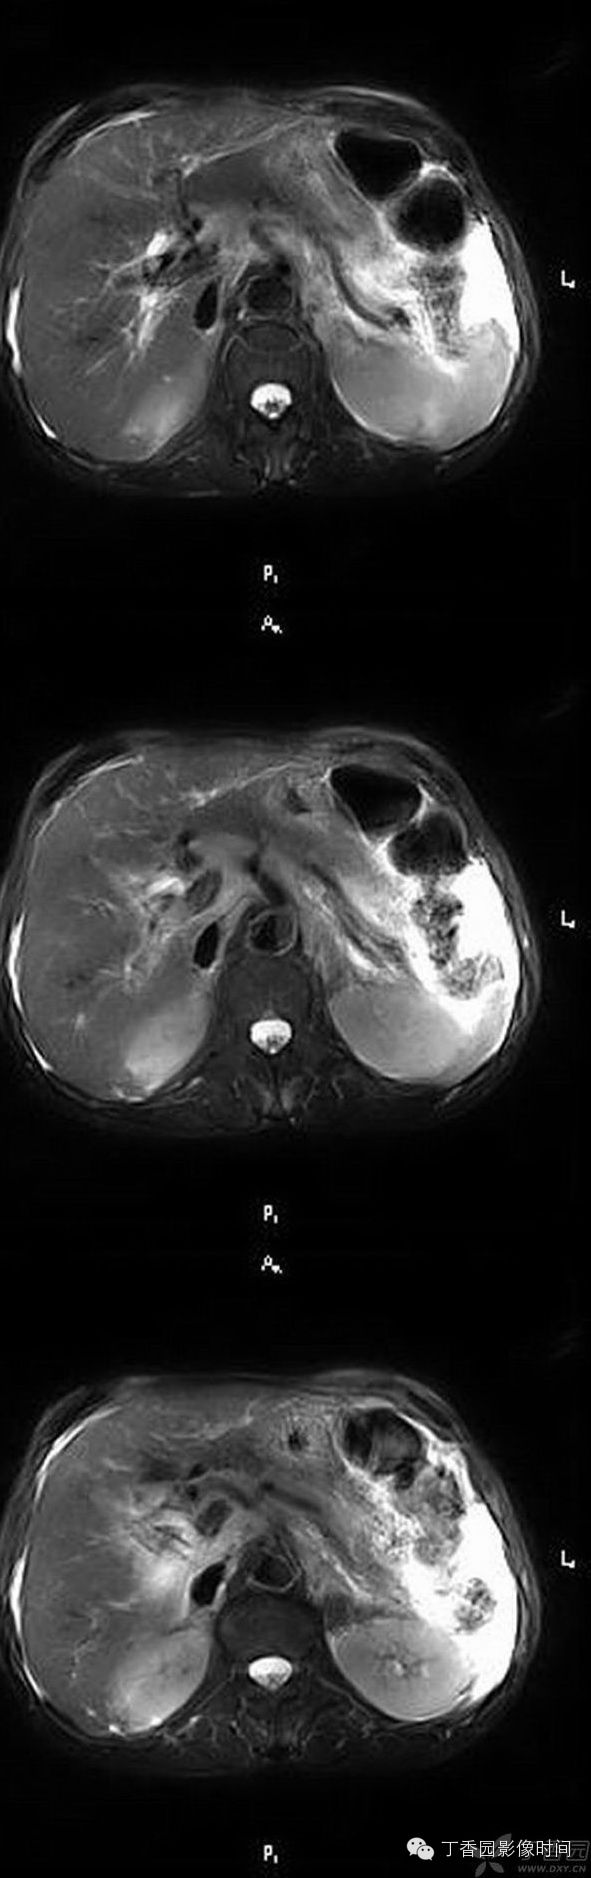

MR表现:

平扫见门静脉正常结构消失、主干和/ 或分支闭塞,门静脉、胆囊周围可见由侧支静脉形成的团块状或网状异常软组织或流空信号影,正常结构模糊紊乱。

增强扫描于门静脉期血管团明显强化, 走行迂曲。

门静脉癌栓于动脉期可轻度强化,相应管径增粗。而门静脉血栓无强化,相应管径无明显增粗。

病例二:男,55岁,肝硬化、脾脏切除并引流术后7年。